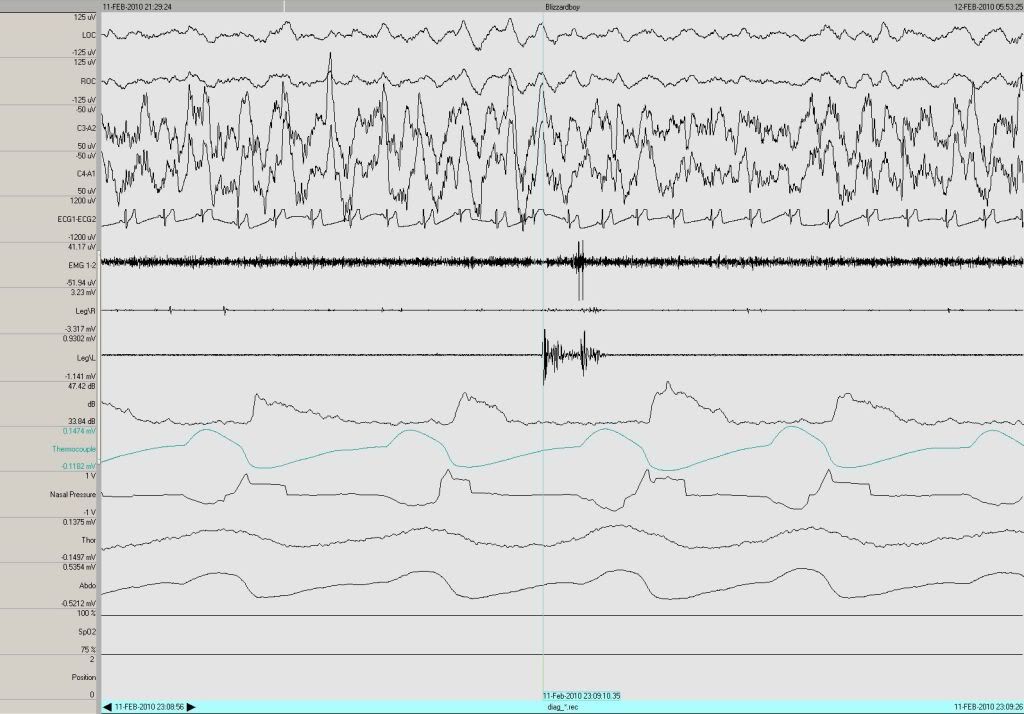

To illustrate this point, let's take a look at some of your SWS and some of the other stuff going on:Muffy wrote:Nothing. You can't tell it's there, SWS just goes merrily chugging along (the sleep stage, not the person).blizzardboy wrote:So what then is the downside of the "infection" of delta wave sleep by alpha waves in terms of sleep architecture?Muffy wrote:And the deep sleep is not "disrupted", it's "infected".

The SWS in continuous without arousal. So here you have alpha intrusion, you got some snoring, probably some flow limitation, and your PLMs, and you're sleeping through the whole thing.

SWS = much stability.

Speaking of which, in the very next epoch, two PLMs being slept through nicely.jnk wrote:...since sleep continues without actual arousal.